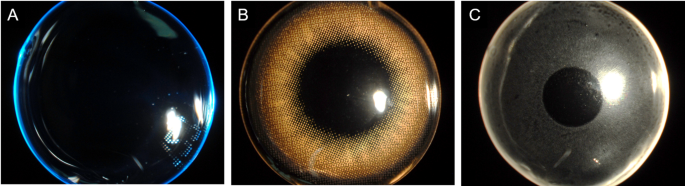

Three types of lenses were used in this study: clear (Fig. 1A), cosmetic (Fig. 1B), and nephrite-embedded contact lenses (Fig. 1C). The clear and cosmetic lenses were commercially available soft contact lenses and served as control groups. The nephrite-embedded contact lens was newly developed in our laboratory using the Flusier method, in which purified nephrite powder was incorporated within the polymer matrix so that nephrite was not directly exposed to the ocular surface. To maintain optical clarity, the central visual axis was intentionally left free of nephrite to maintain transparency and normal vision. Optical transmittance of the contact lenses was evaluated according to ISO 18,369 standards by an accredited testing laboratory (Korea Testing & Research Institute). The visible light transmittance measured at the central optical zone was 99%.

Three types of contact lenses used in this study. (A) Clear contact lens, (B) Cosmetic contact lens, and (C) Nephrite-embedded contact lens.